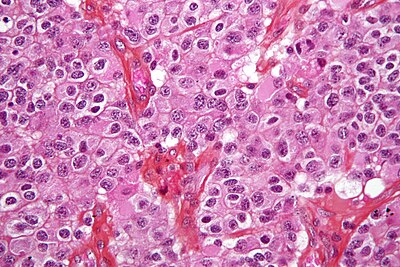

1

Diagnosis?

Epitheloid glioblastoma HE.jpg

Pilocytic astrocytoma

Diffuse Astrocytoma

Pleomorphic xanthoastrocytoma

Subependymal giant cell astrocytoma

Oligodendroglioma

Glioblastoma, classic

Glioblastoma, epitheloid

Giant cell glioblastoma

Gliosarcoma

Ependymoma

Subependymoma

Myxopapillary ependymoma

Ganglioglioma

Choroid plexus papilloma

Angiocentric glioma

Dysembryoplastic neuroepithelial tumour

Neurocytoma

Paraganglioma

Pineocytoma

Papillary glioneuronal tumour

Medulloblastoma

CNS PNET